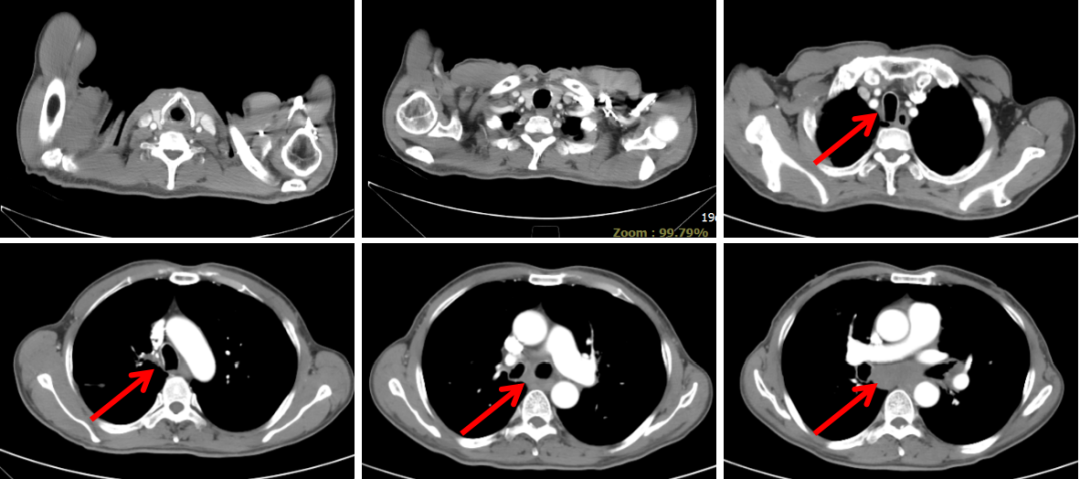

胸部CT(2020-03-03):左肺靶病灶直径59 mm,纵隔3、7区及双侧肺门淋巴结病灶直径20 mm(图1)。

图1:2020年6月7日,治疗前PET-CT

本例患者为左肺中心性鳞癌(cT4N3M1c,IVb期),伴多发淋巴结转移、左肺转移。经替雷利珠单抗联合化疗治疗,2个周期后左肺病灶和多发淋巴结转移病灶直径均明显缩小,疗效评价达到PR。患者目前已联合用药4周期,疗效持续PR,PFS近3个月,病情平稳,治疗过程中未出现明显消化道反应及骨髓抑制,安全性良好。